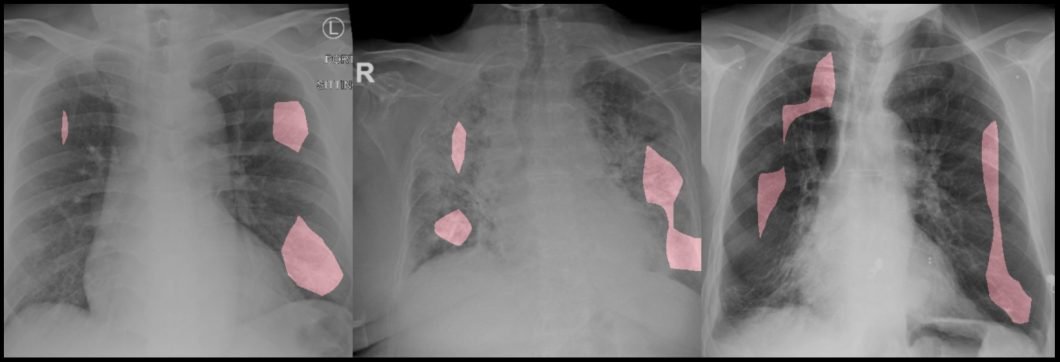

COVID-NET example for computer vision to detect shadows in lung tissue

4. Cancer Detection with Computer Vision

Remarkably, deep-learning computer vision models have achieved physician-level accuracy at diagnostic tasks such as identifying moles from melanomas. Skin cancer, for instance, can be difficult to detect in time as the symptoms often resemble those of common skin ailments. As a remedy, scientists have taken the help of computer vision applications to differentiate between cancerous skin lesions and non-cancerous lesions effectively.

AI research has also identified the numerous advantages of using computer vision and deep learning applications to diagnose breast cancer. Trained with a vast database of images consisting of both healthy and cancerous tissue, it can help automate the identification process and reduce the chances of human error.

With the rapid improvements in technology, healthcare computer vision systems may be used for diagnosing other types of cancer, including bone and lung cancer, in the near future.

Lung cancer classification model to analyze CT medical imaging